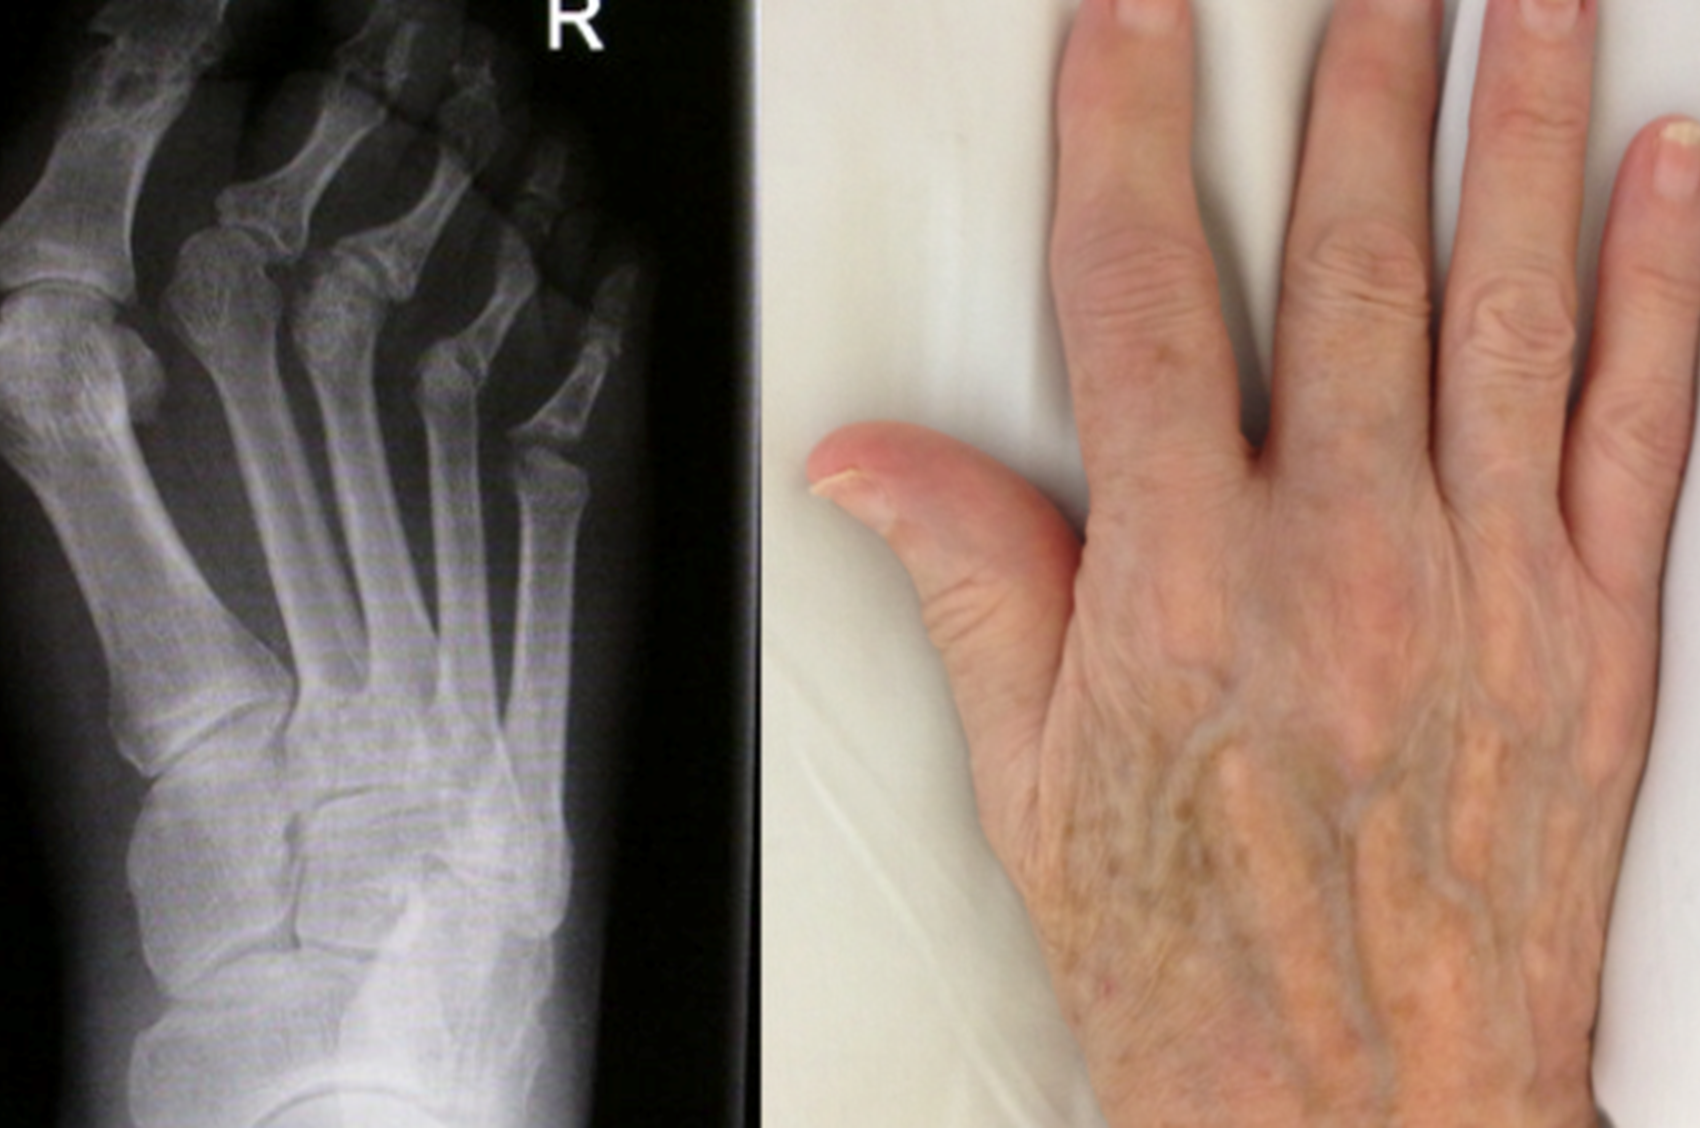

In the UK, more than 10 million people have arthritis or other similar conditions affecting their joints. Psoriatic arthritis is a type of inflammatory arthritis linked to the skin condition psoriasis.

Around 1/3 of people with psoriasis may go on to develop arthritis over time. Laura Coates will review current research projects running in the clinics at the Nuffield Orthopaedic Centre aiming to improve patient outcomes for those with psoriatic arthritis in Oxford and beyond.